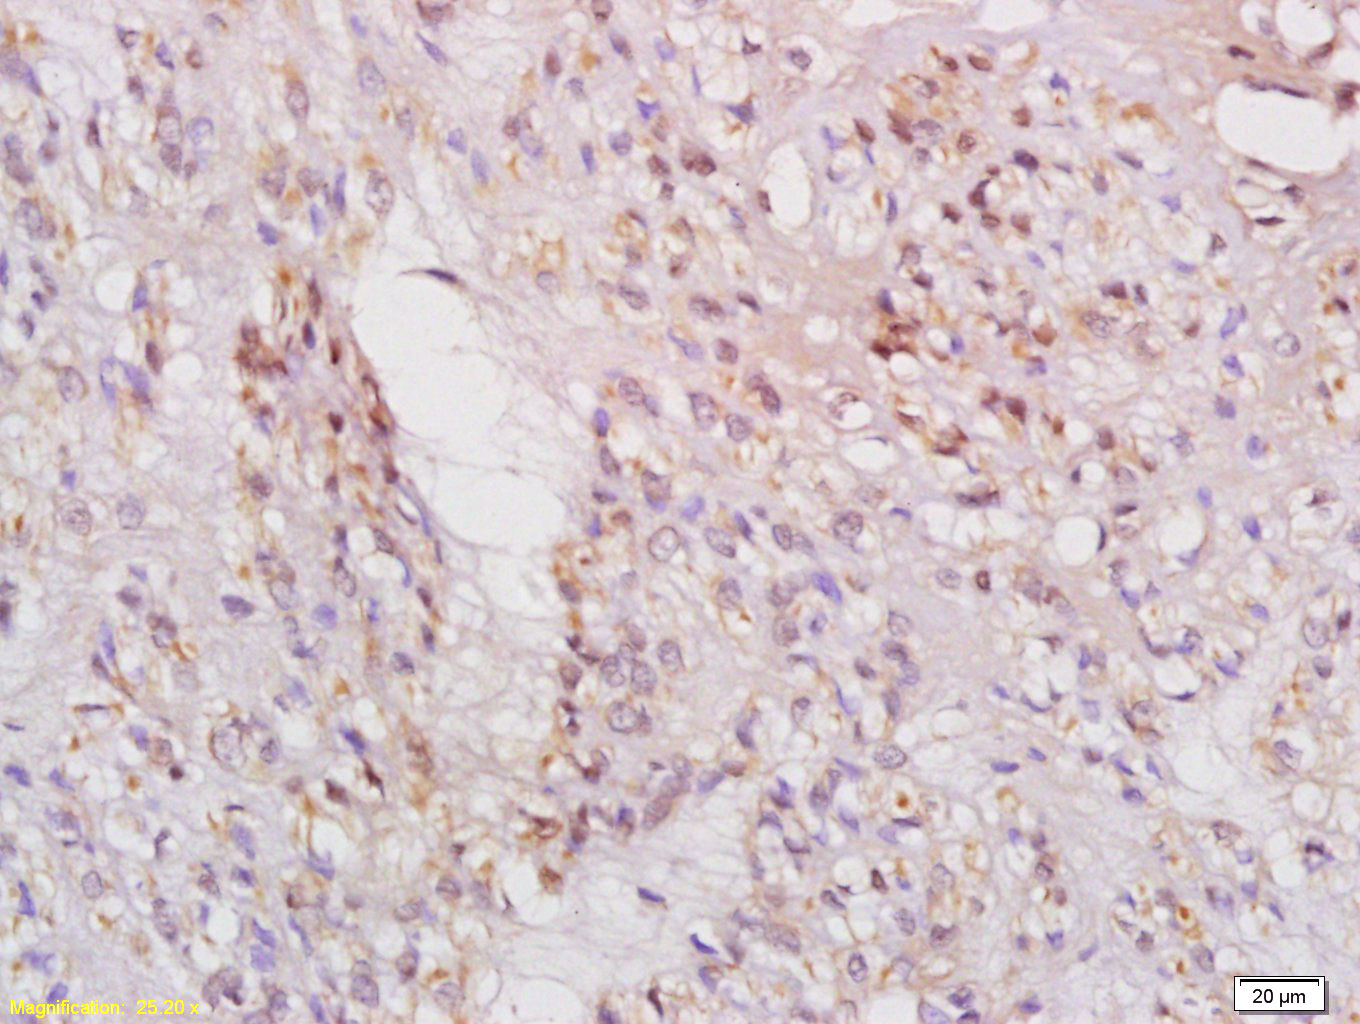

Antigen retrieval: citrate buffer ( 0.01M, pH 6.0 ), Boiling bathing for 15min; Block endogenous peroxidase by 3% Hydrogen peroxide for 30min; Blocking buffer (normal goat serum,C-0005) at 37℃ for 20 min;

Incubation: Anti-phospho-IRS1(Ser636/639) Polyclonal Antibody, Unconjugated(bs-3201R) 1:200, overnight at 4°C, followed by conjugation to the secondary antibody(SP-0023) and DAB(C-0010) staining